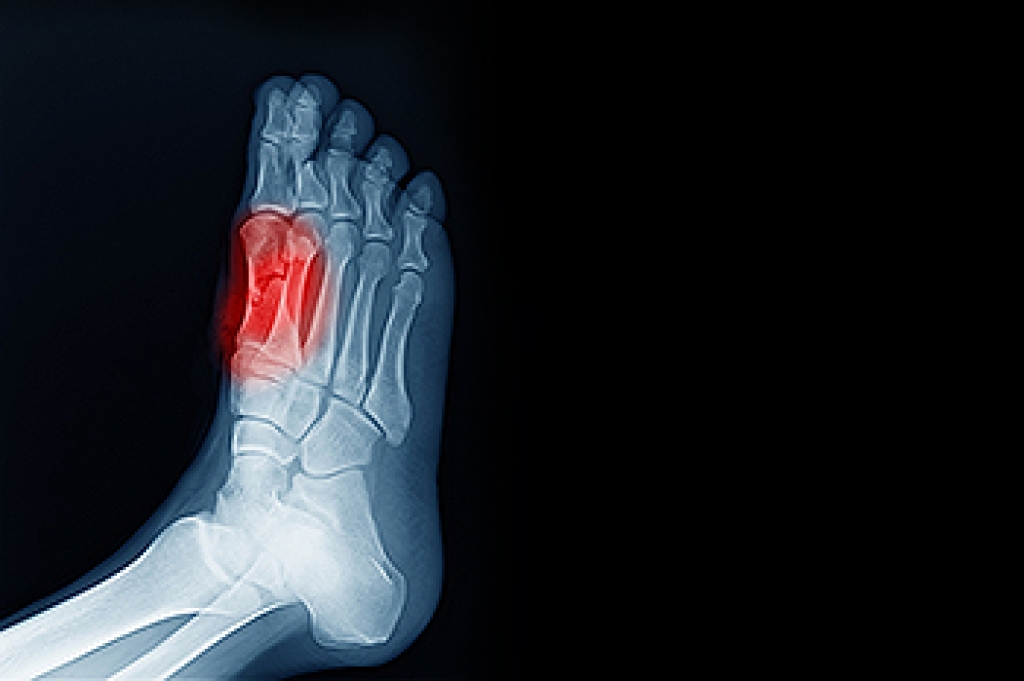

A broken foot requires immediate medical attention and treatment. If you need your feet checked, contact one of our doctors from Advanced Foot & Ankle Medical Center. Our doctors can provide the care you need to keep you pain-free and on your feet.

Broken Foot Causes, Symptoms, and Treatment

A broken foot is caused by one of the bones in the foot typically breaking when bended, crushed, or stretched beyond its natural capabilities. Usually the location of the fracture indicates how the break occurred, whether it was through an object, fall, or any other type of injury.

Those that suspect they have a broken foot shoot seek urgent medical attention where a medical professional could diagnose the severity.

Treatment for broken bones varies depending on the cause, severity and location. Some will require the use of splints, casts or crutches while others could even involve surgery to repair the broken bones. Personal care includes the use of ice and keeping the foot stabilized and elevated.